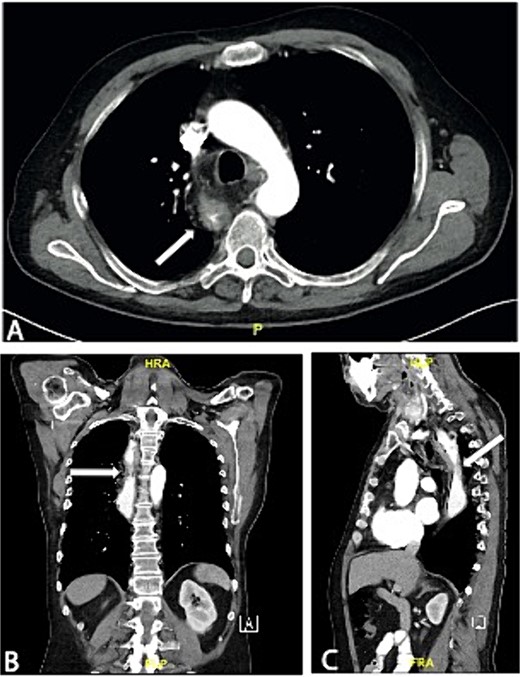

We report the case of a 57-year-old patient who presented to our institution with histologically confirmed colorectal adenocarcinoma of the interposed colon after esophagectomy in infancy. At the age of 6 months, the patient underwent surgery for esophageal atresia with resection and colonic interposition. At the age of 4 years, a segment of the interposed colon was resected, most likely due to kinking. No records on these operations performed at a renowned institution in Germany around 1965 exist anymore. In December 2021, the patient presented with hematin reflux via an inserted gastric tube and underwent esophago-gastro-duodenoscopy, while he was hospitalized for myocardial infarction. A hemorrhage in the area of the intestinal interposition was clipped, but there were abnormalities of the mucosa of unclear dignity, which is why a upper endoscopy was repeated after discharge. The examination in August 2022 revealed a mass 23 cm from the incisors, occupying about one-third of the circumference (Fig. 1). The histological workup of the samples taken showed colonic mucosa including a colorectal adenocarcinoma. Staging CT scans of the thorax and abdomen revealed marked wall thickening of the neoesophagus proximal to the tracheal bifurcation over ~7.5 cm (Fig. 2). There was no evidence of suspicious pulmonary or hepatic lesions. Thus, the patient was planned for primary surgical resection, in accordance with the standard approach for colon cancer, after discussion in our multidisciplinary team meeting. The patient underwent thoracoabdominal esophagectomy with resection of the colonic interposition en bloc with adjacent healthy esophagus orally and distally. Reconstruction was performed by gastric pull-up. Due to the previous surgery, marked adhesions in the thorax were encountered and lead to an intraoperative injury of the lung, resulting in an atypical lung resection of the right upper lobe. Histological examination of the surgical specimen revealed moderately differentiated colorectal adenocarcinoma with lymphogenous metastasis (G2, pT3, pN2a (4/13), L0, V0, Pn0, R0, cM0). Approximately 2 months after surgery, adjuvant chemotherapy with CAPOX (capecitabine and oxaliplatin) was started.

Axial (A), coronal (B), and sagittal slice (C) of a preoperative CT scan showing wall thickening of the neoesophagus proximal to the tracheal bifurcation.